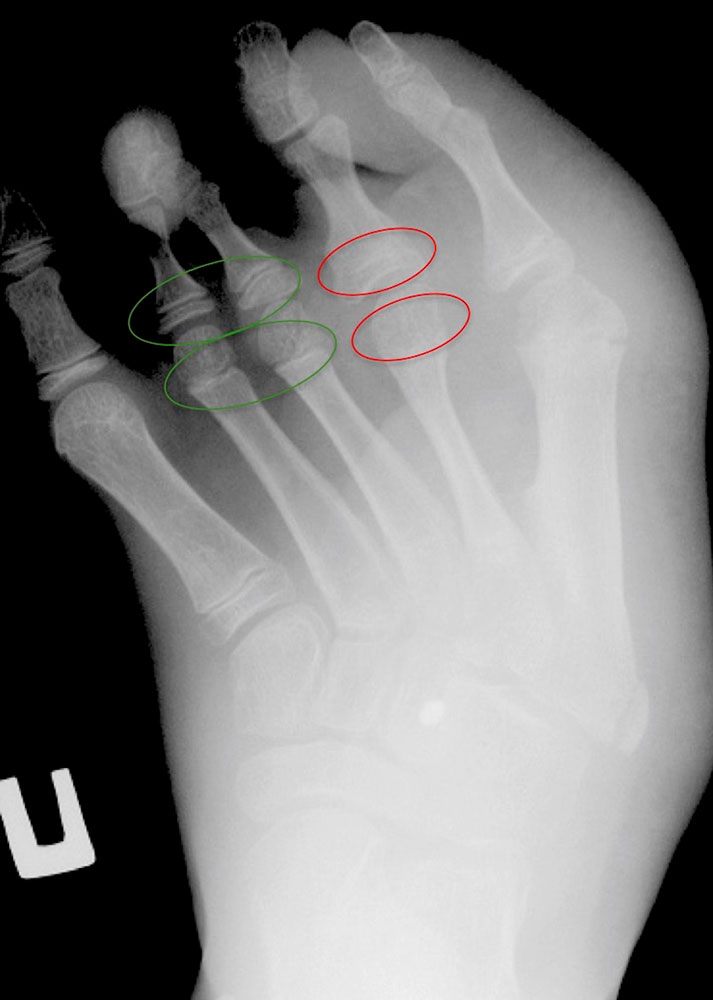

Hyperplasias lead to accelerated growth of the bone and can in principle affect all bones. There are forms in which the increased growth is distributed evenly over the entire bone, e.g., the thigh, lower leg and foot are proportionally lengthened, but there are also forms in which there is disproportionate, circumscribed overgrowth.

Hyperplasia of the extremity may be present in slow-flow malformations, i.e., venous, capillary and lymphatic malformations, as well as in arteriovenous (fast-flow) malformations.

Combination of hypoplasia and hyperplasia

As mentioned, hypotrophy can also occur as a result of inactivity in the case of chronic pain or after surgery. In patients who show accelerated bone growth in association with vascular malformations on the one hand, and inactivity hypotrophy as a result of pain on the other, lengthening of the limb with decreased circumference is often found as a consequence. Wearing compression garments with a high compression class at an early age can also contribute to a reduction of circumference. Especially in CLOVES syndrome, patients may present with a primary combination of circumscribed overgrowth, e.g., of the foot, combined with undergrowth (hypoplasia), e.g., of the upper chest or one or both arms.